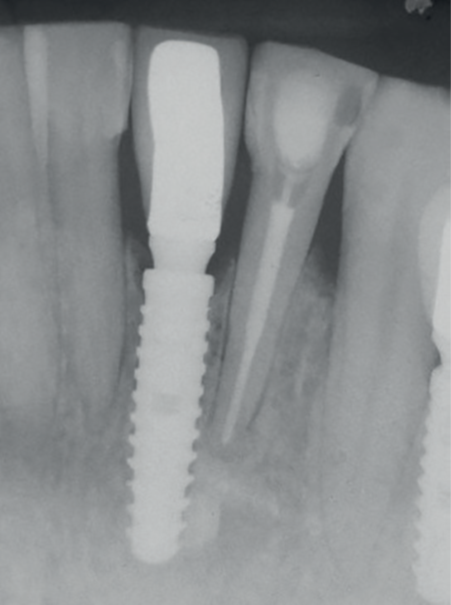

Na consulta seguinte, a coroa metalocerâmica com liga de níquel-cromo foi instalada no elemento 41 e o orifício de acesso do parafuso foi restaurado com resina composta (Z350, 3M). Uma radiografia periapical foi realizada para posterior controle (Figuras 13 a 15). Após 12 meses, com uma nova avaliação clínica e radiográfica, observou-se a boa manutenção dos tecidos peri-implantares (Figuras 16 e 17).